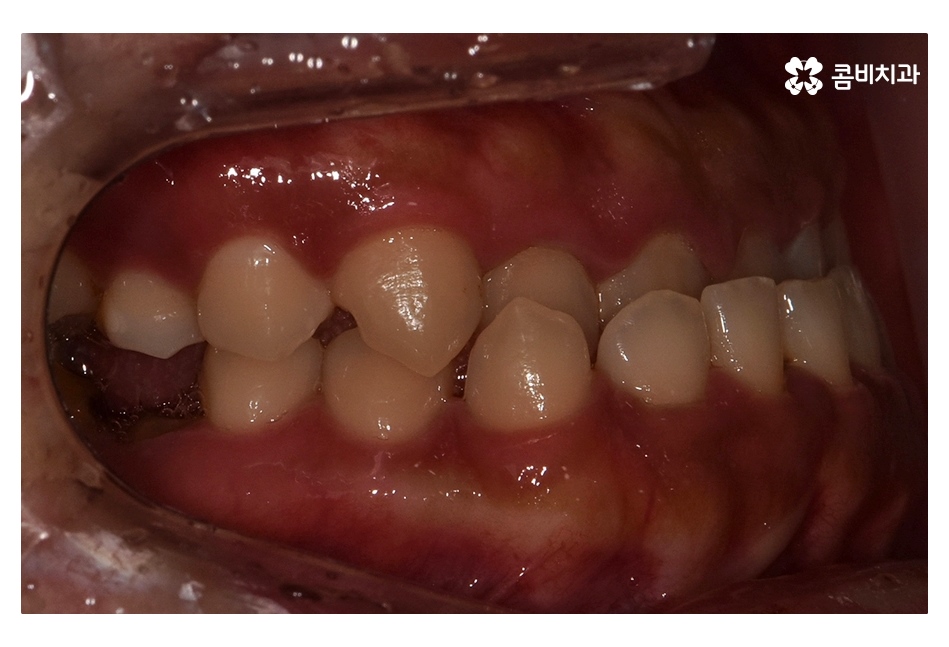

위 환자분의 경우 충치로 인해 오른쪽 아래 제1대구치와

왼쪽아래 제2대구치가 상실된 상태였으며, 치아교정만으로는

치료가 불가능한 케이스였기 때문에 비발치 교정으로

진행하면서 외과수술이 병행된 케이스라고 할 수 있어요

클리피씨교정을 통해서 약 1년 6개월간

치료가 진행이 되었고, 수술과 병행이되며, 치료 마무리 단계에서

임플란트 수술까지 진행이 된 사례라고 볼 수 있는데요.